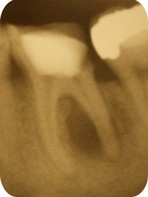

Tento výkon je tiež nutné vykonať pri liečbe infekcie na hrote koreňa zuba. Koreňové kanáliky je nutné rozšíriť na potrebnú veľkosť, prečistiť a hermeticky uzatvoriť (definitívne endodontické ošetrenie). V niektorých prípadoch nie je možne definitívne ošetrenie koreňových kanálikov pri jednej návšteve, napr. ak je prítomná infekcia na hrote koreňa zuba chronická periodontitída.

V takýchto prípadoch sa na určité obdobie aplikuje do koreňových kanálikov tzv. dezinfekčná vložka, a zub je uzatvorený provizórnou výplňou na dobu potrebnú k vyliečeniu infekcie. Väčšina endodonticky ošetrených zubov má dobrú prognózu, a takto ošetrený zub si aj naďalej plní svoju funkciu. Úspešnosť týchto zákrokov je veľmi vysoká.